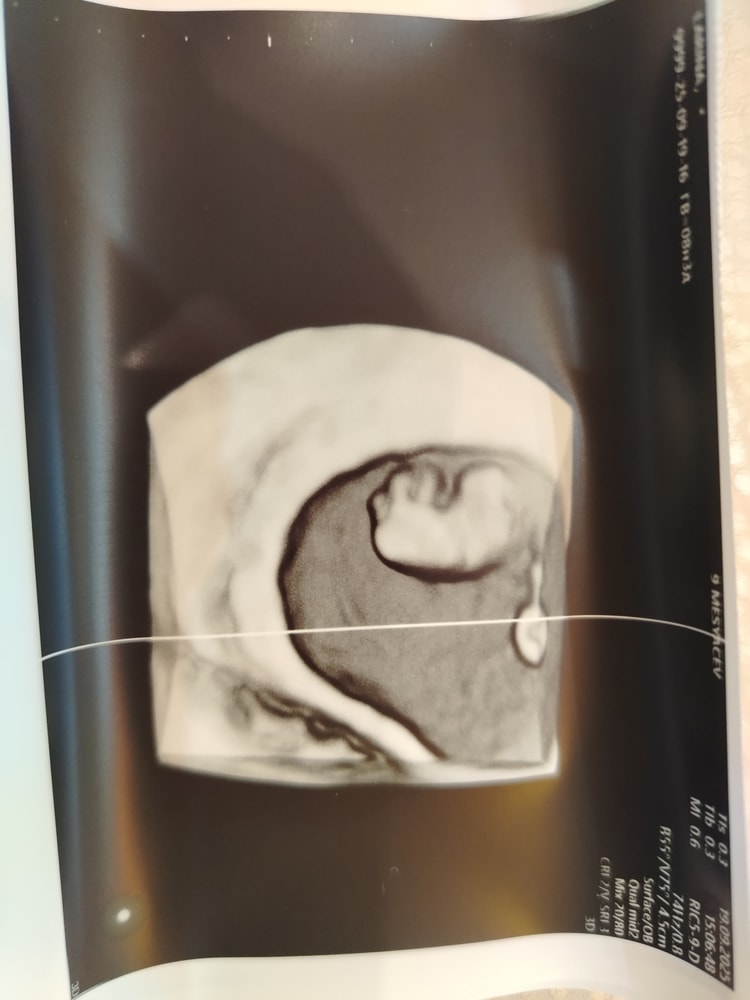

Наталья, сейчас скину. Тут КТР 2.2 см. Срок 8.6. Плодное 4.3 см.

25 мм у меня было в 6.5 недель в прошлую беременность. Когда КТР был 0.88 см.

Джеллибин, ну по размером примерно одинаково. Небольшая разница. Надеюсь, что неправильно измерили, потому что по 3д снимку там много места. Ну посмотрим, записалась на вторник на УЗИ ещё.